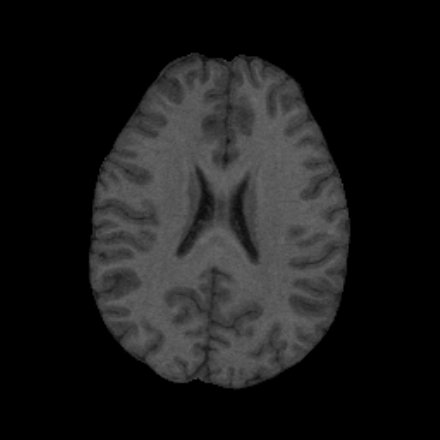

• use magnetic resonance (MR) images to display anatomical information (see Figure 1)

MR Scan from One Subject MR Scan from a Second Subject

Figure 1: MR image scans from two different subjects illustrate the variability in anatomical structure between individuals.